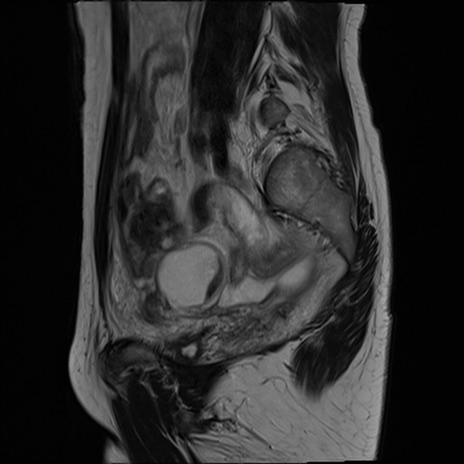

症例39 T2WI(矢状断像)

MRI(4日後)